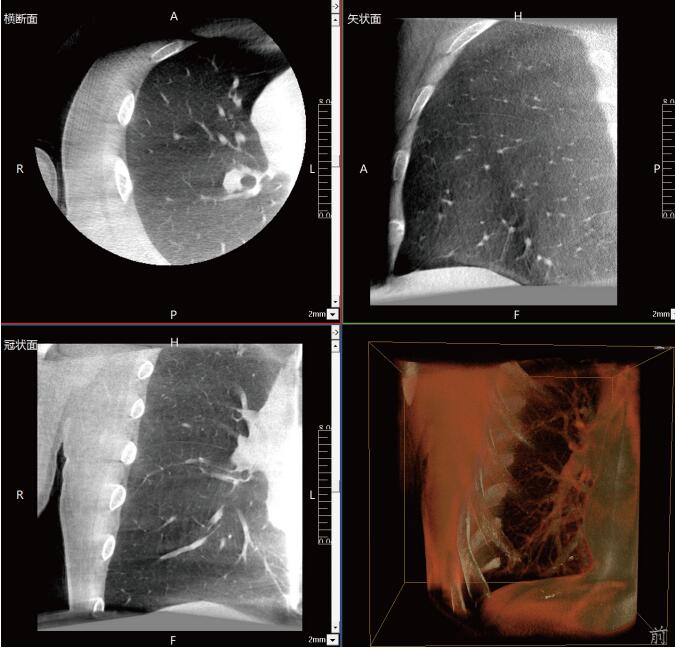

此外,在呼吸介入領(lǐng)域也展現(xiàn)出巨大潛力。它能幫助醫(yī)生完成肺結(jié)節(jié)的精準(zhǔn)定位及切除手術(shù),避免患者需要在CT室和手術(shù)室之間轉(zhuǎn)移,減少了患者的痛苦,也顯著降低了出血、氣胸等并發(fā)癥的發(fā)生機率。